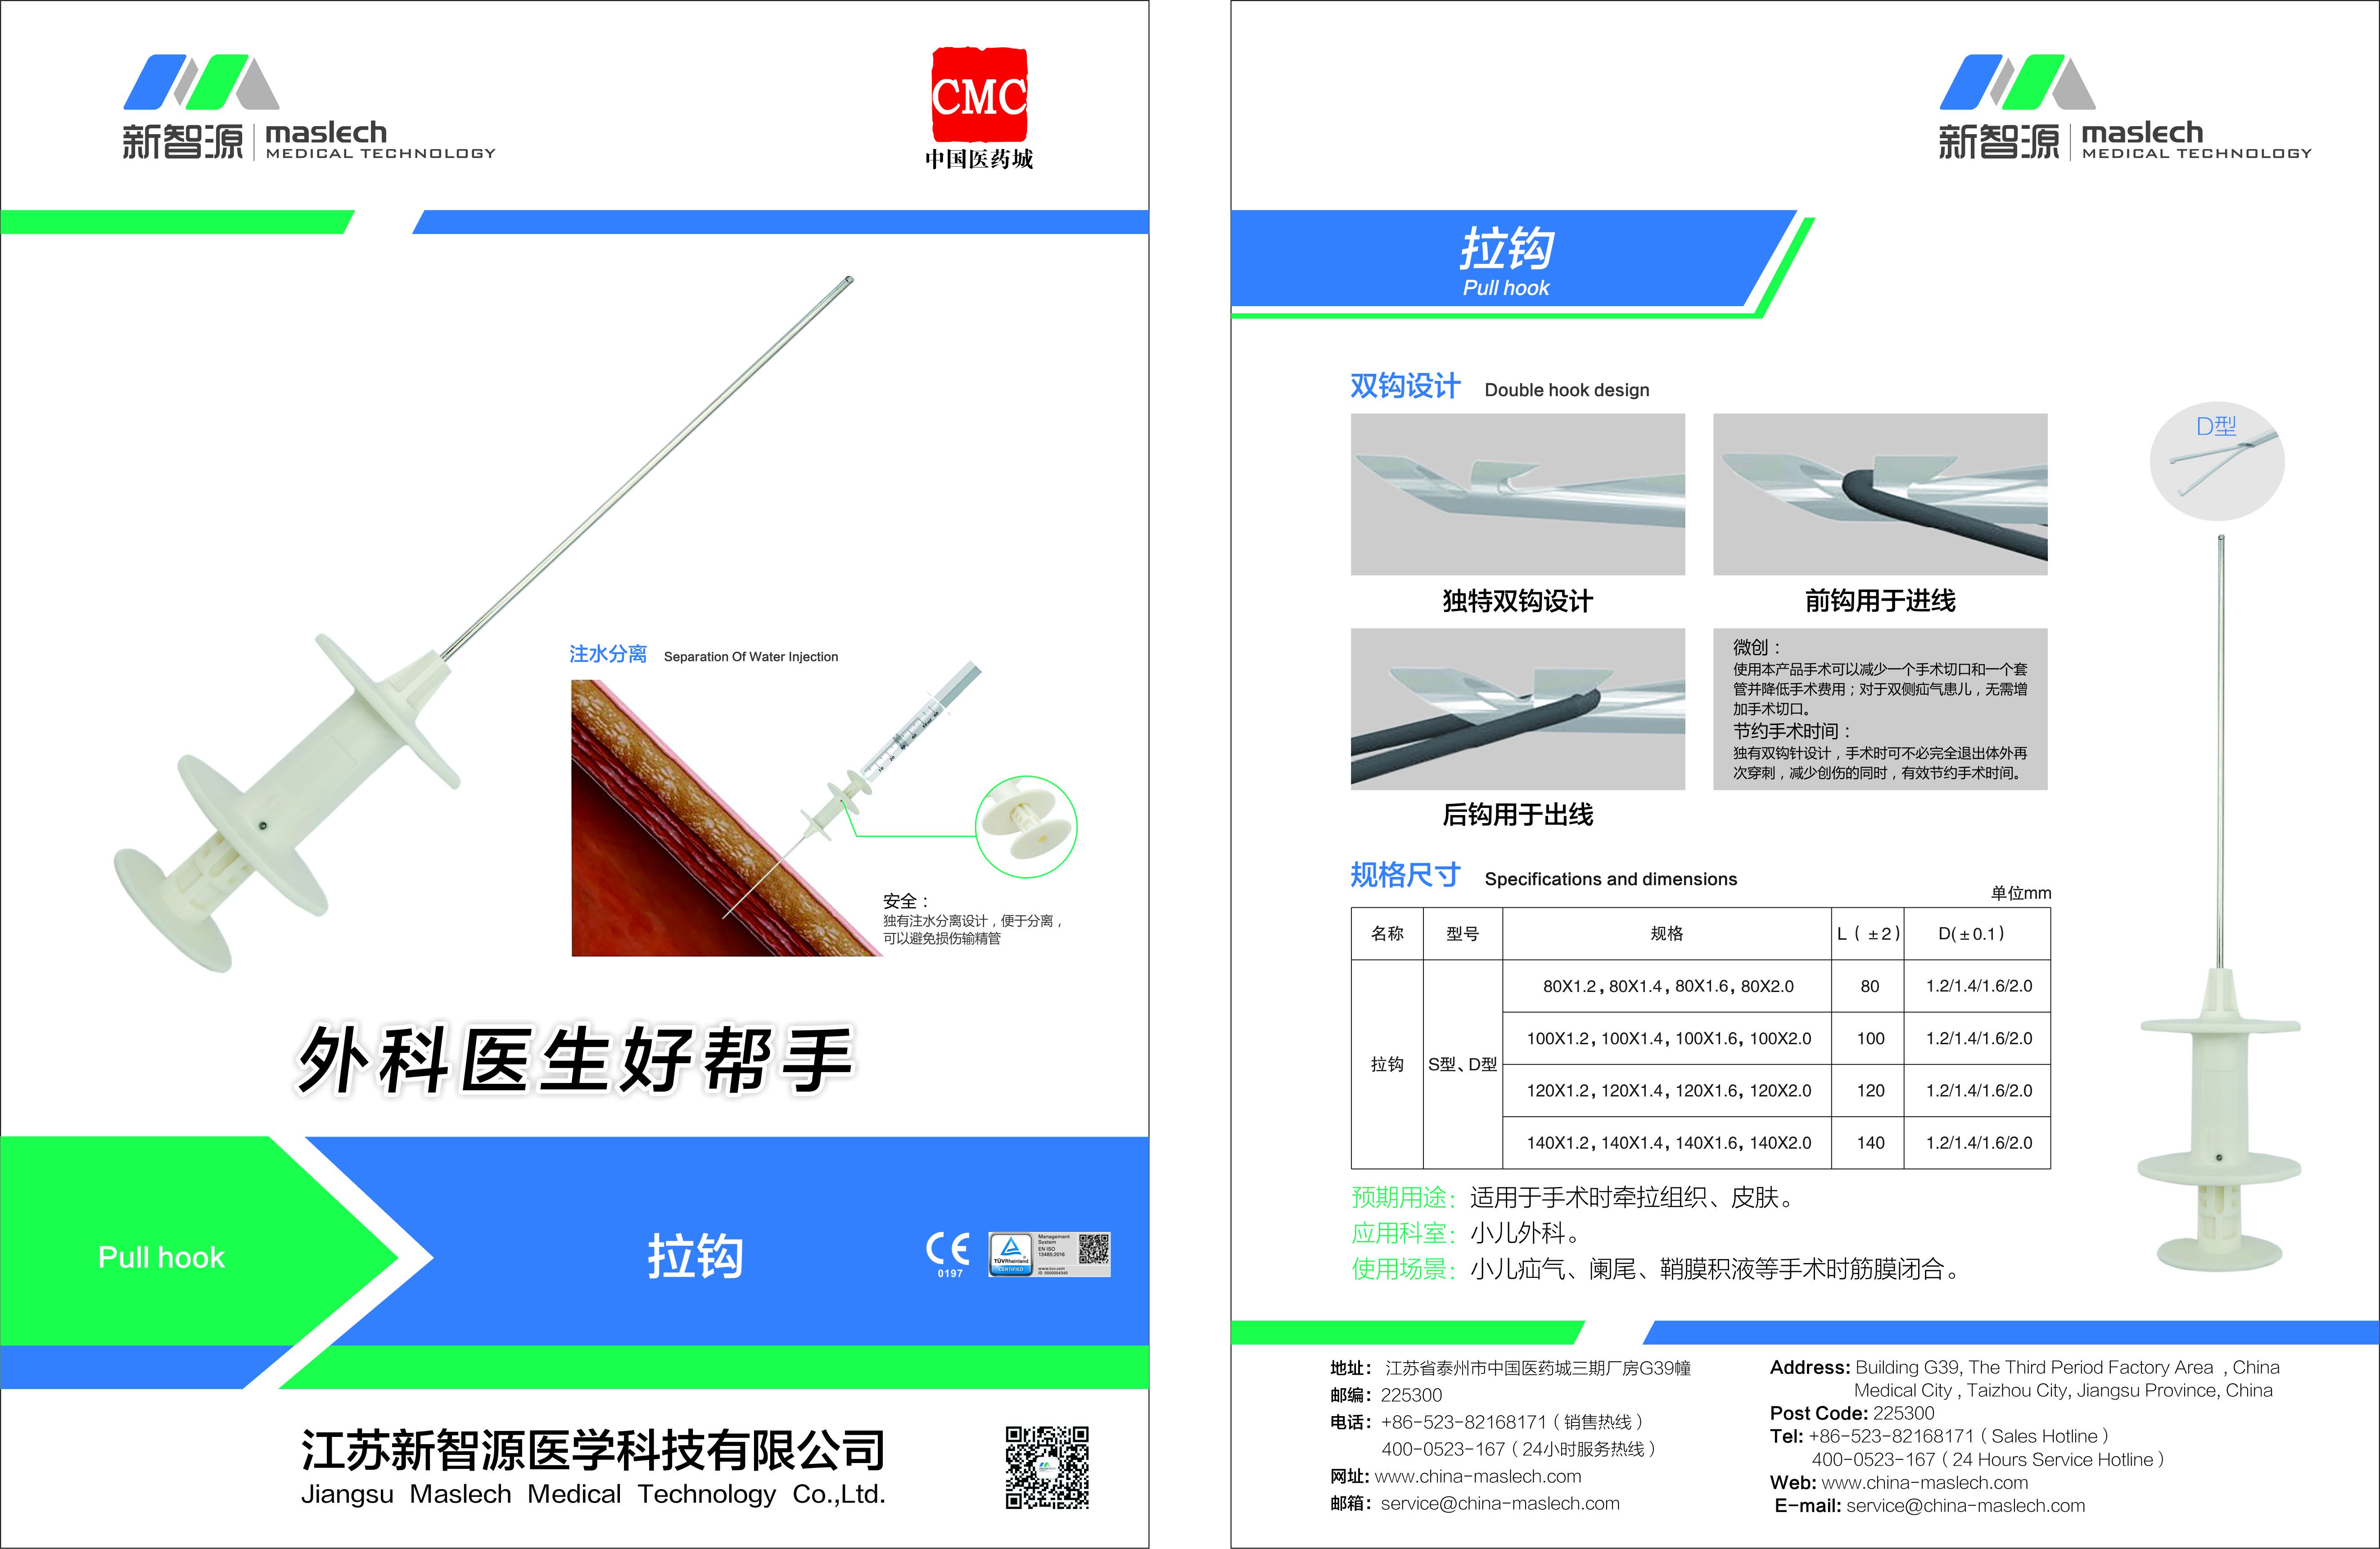

拉鉤產(chǎn)品說明: